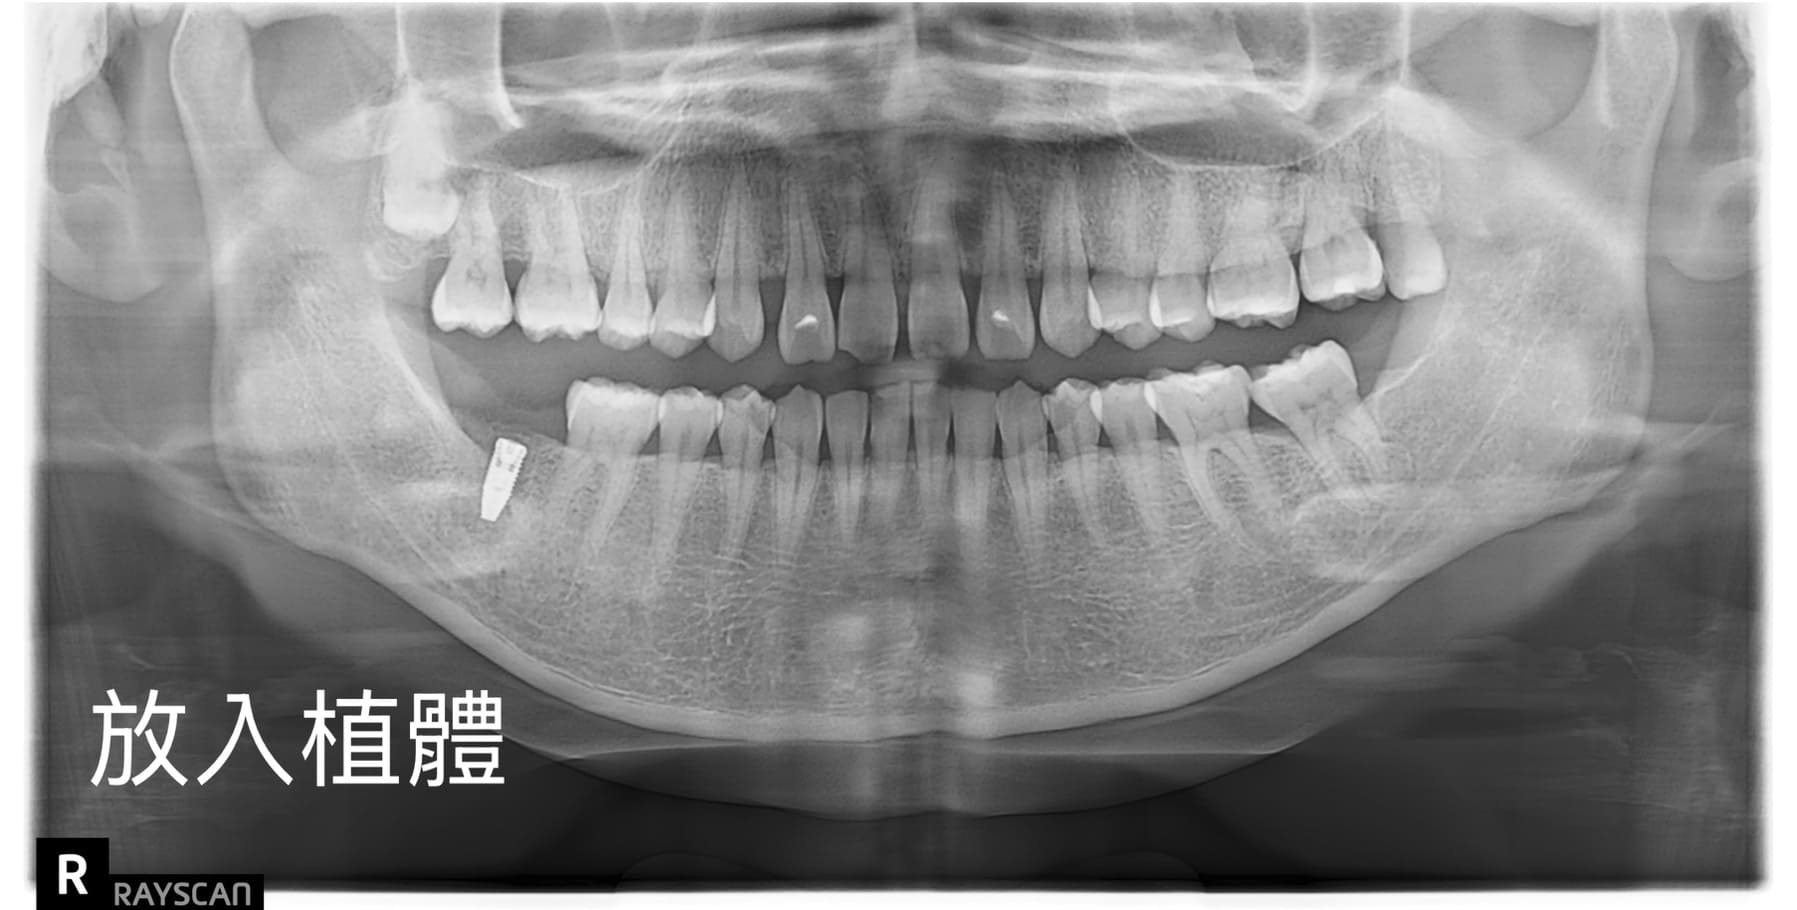

適采牙醫診所數位植牙案例

.jpg)